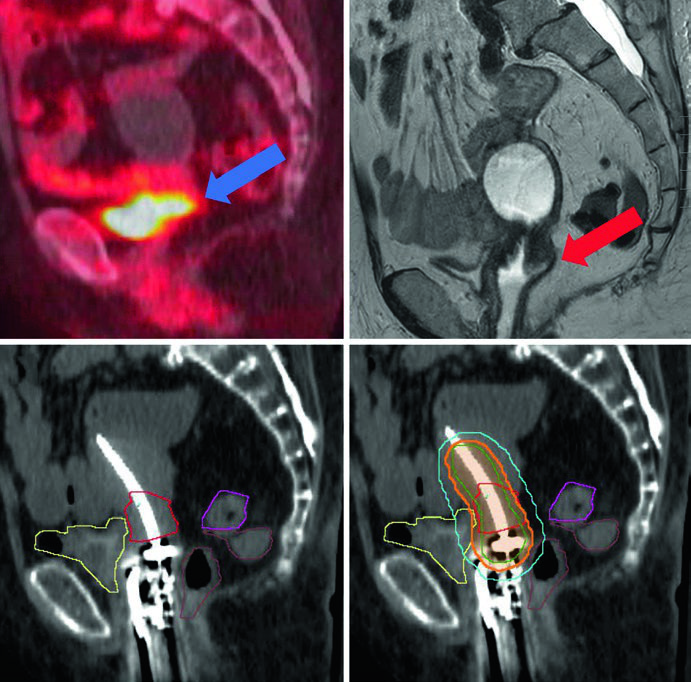

Os volumes-alvo seguem a terminologia GEC-ESTRO. O GTV corresponde ao tumor macroscópico visível na RM no momento da braquiterapia. O HRCTV engloba o GTV, colo uterino e extensão macroscópica ou envolvimento parametrial ao tempo do implante. O IRCTV adiciona 1 cm de margem ao HRCTV e pode incluir a extensão da doença ao diagnóstico — usado mais na Europa do que nos EUA.

Quando se utiliza TC para planejamento, os volumes-alvo tendem a superestimar a extensão da doença. A RM permite definir o GTV com muito mais acurácia. Para câncer cervical pós-operatório com margem vaginal positiva, trata-se o terço superior da vagina.